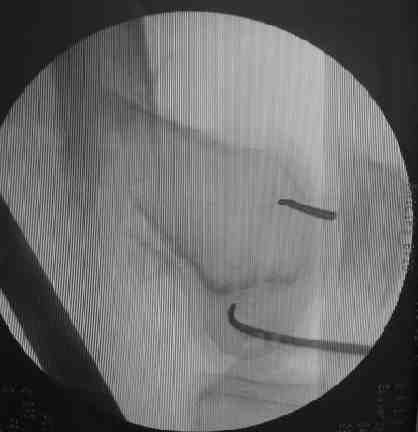

Если перелом диафизарный, в периферическом отломке достаточно одной спицы в переднем отделе мыщелков. Если более дистальный - вводим 2 спицы, ближе к фокусам кондилярного "эллипса". Так они не мешают ни анте-, ни ретроградному введению (см. картинку)

.